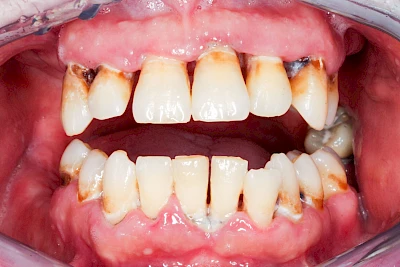

Bakterien in den Zahnbelägen greifen neben den Zähnen auch das Zahnfleisch (Gingiva) und den gesamten Zahnhalteapparat (Parodont) an. Der Körper reagiert mit einer Entzündung, sichtbar als Rötung und Schwellung. Meist blutet das Zahnfleisch z .B. beim Essen oder auch beim Putzen der Zähne.

Ist zunächst nur das Zahnfleisch von der Entzündung betroffen, spricht man von Gingivitis. Später, wenn auch der Knochen um die Zähne herum entzündet ist, spricht man von einer Parodontitis. Bei der Parodontitis wird der Knochen nach und nach abgebaut und das Zahnfleisch zieht sich zurück. Die Zahnhälse und Zahnwurzeloberflächen liegen mehr und mehr frei. Die Zähne werden zunehmend lockerer und fallen schließlich aus.